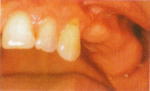

歯の無い部分が広い場合

臼歯が失われた場合、従来は取り外し式の部分入れ歯で咬合機能を回復させてきました。

一方、インプラントなら天然歯と同等の感覚の固定式人工歯を入れることができます。